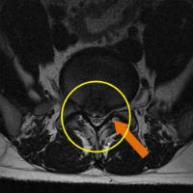

MRI